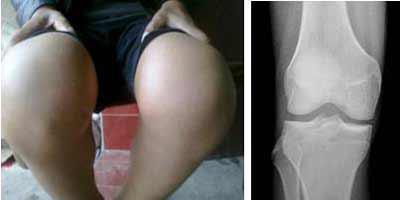

(图:患者治疗后膝关节红肿消失,屈伸自如)

治疗四十分钟后,赵先生就感觉四肢关节疼痛减轻了不少。两个疗程的治疗后,赵先生膝关节肿胀消除,关节处未见皮肤发红,关节晨僵现象消失,四肢关节活动自如,膝关节能够自由屈伸。

陈建春主任采用西南地区全力引进的HD-热层析检测系统,检测患者关节炎性介质消失,四肢关节无疼痛现象。